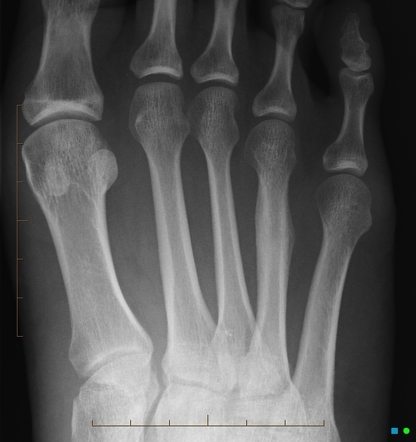

JONES

- Transverse fracture of the fifth metatarsal base, occurring at least 15 mm distal to the proximal end of the bone, distal to the insertion of the peroneus brevis

How well did you know this?